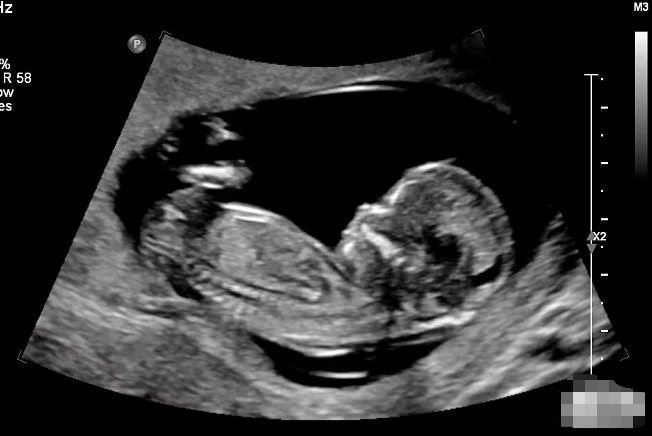

三个月胎儿彩超图片可见胎儿已发育成具有人体各重要部位及胎儿附属器的胎儿结构。

三个月胎儿彩超检查时可见卵黄囊基本已退化。取胎儿正中矢状切面图像,可见胎体呈水平位自然屈曲,胎儿头顶部弧形边缘及下腹部生殖结节可清晰显示。颈后部显示皮下组织、皮肤、羊膜形成的三条强回声带。在胎头丘脑水平横切面,可显示双侧丘脑对称,脑中线完整居中。胎儿心脏切面,可观察到胎体内有节律的心脏搏动,

三个月胎儿彩色超声检查可测量胎儿生物学参数,用以准确估算孕周。同时能观察胎儿头颅、躯干、肢体等大体结构,筛查严重的胎儿结构异常胎儿。测量胎儿颈部透明层厚度(NT),可有助于进行胎儿染色体异常的早期筛查。